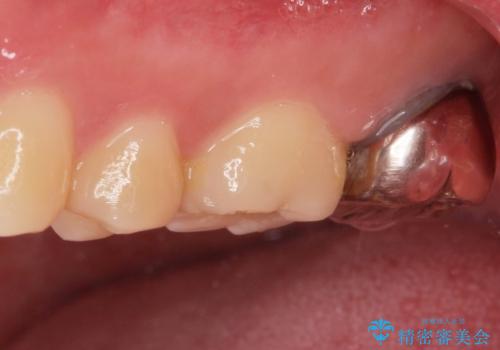

白い物で治療して欲しいとのことで、セラミックの詰め物だと詰め物の範囲が大きく、割れてしまう可能性があるので

ジルコニアクラウン(被せもの)で治療を行いました。

- 仮歯・ジルコニアクラウン 12.1万円費用は治療当時の料金となります